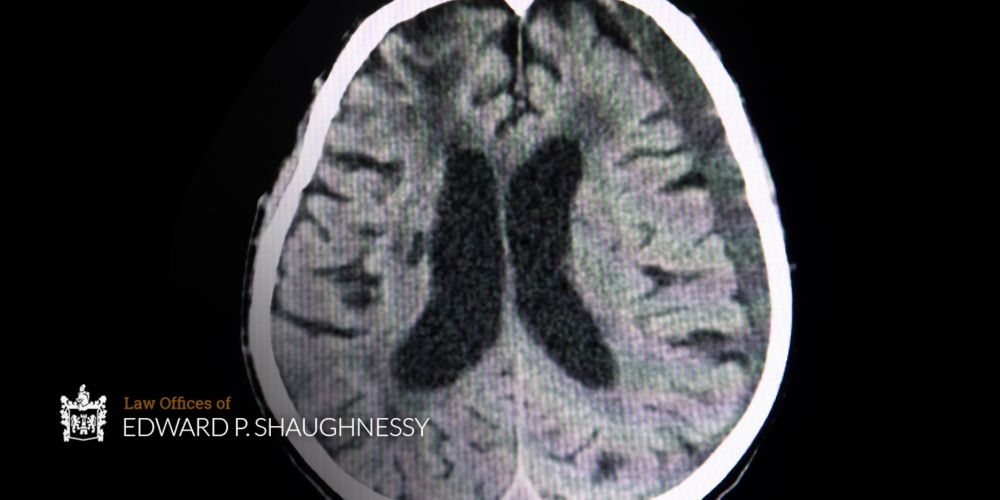

Subdural hematomas can present like stroke, brain tumors, dementia, or psychiatric conditions. The gradual onset of symptoms in chronic cases can be mistaken for normal aging or depression, particularly in elderly patients. Prompt identification can mean the difference between full recovery and permanent disability or death. CT scans quickly reveal blood in the subdural space and brain compression. MRI provides more detailed images, particularly useful for smaller or chronic hematomas.